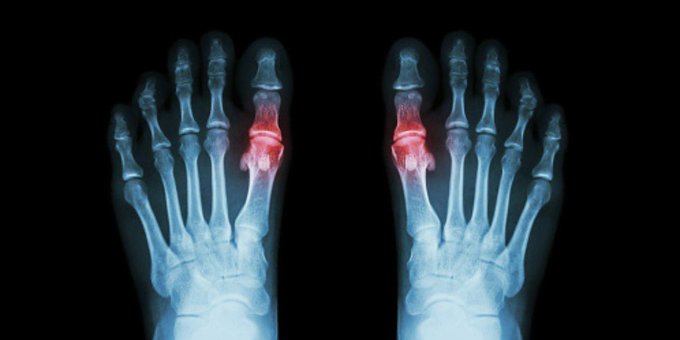

La gota es una forma común y dolorosa de #artritis Sus síntomas incluyen hinchazón, enrojecimiento, calor y rigidez en las articulaciones. Más aquí ow.ly/wd6b50x1507